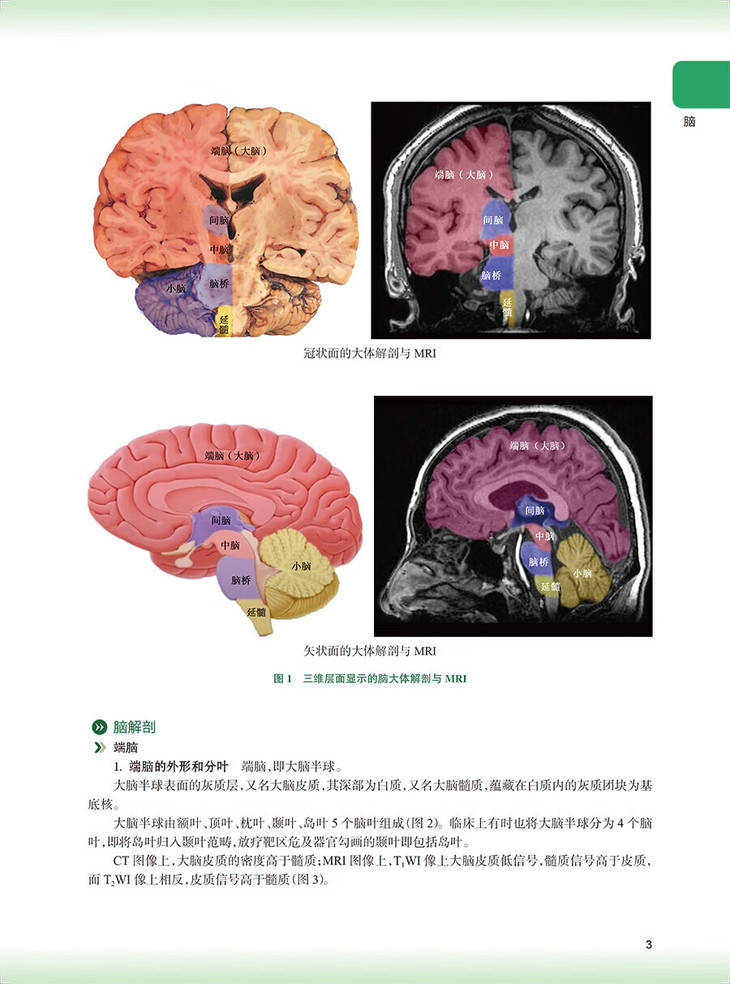

脑/1